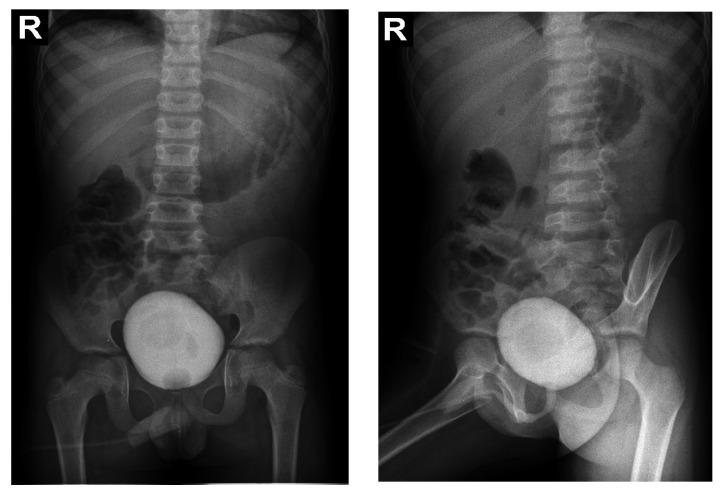

Fabry disease is an X-linked lysosomal storage disease, second in prevalence after Gaucher disease. The onset of symptoms occurs in childhood or adolescence with palmo-plantar burning pains, hypo hidrosis, angiokeratomas, and corneal deposits. In the absence of diagnosis and treatment, the disease will progress to the late phase, characterized by progressive cardiac, cerebral and renal damage, and possible death. We present the case of an 11-year-old male boy who was transferred to the Pediatric Nephrology Department for palmo-plantar burning pain and end stage renal disease. Following the evaluations for the etiology of end stage renal disease we excluded the vasculitis, the neurologic diseases, extrapulmonary tuberculosis. Because of suggestive aspect at CT scan and lack of etiologic diagnosis of renal insufficiency we performed lymph node and kidney biopsy, with a surprising result for storage disease. The specific investigation confirmed the diagnosis.

法布里病是一种 X 连锁溶酶体贮积病,其发病率仅次于戈谢病。症状发作发生在儿童或青少年时期,伴有手掌-足底烧灼感、少汗、血管角质瘤和角膜沉积物。如果不进行诊断和治疗,疾病将进展到晚期,特征为进行性心脏、大脑和肾脏损伤,可能导致死亡。我们报告了一例 11 岁男性患儿,因手掌-足底烧灼感和终末期肾病转入儿科肾病科。在排除血管炎、神经系统疾病和肺外结核等终末期肾病病因后,我们进行了 CT 扫描检查和淋巴结及肾脏活检,结果提示贮积病,特异性检查证实了这一诊断。